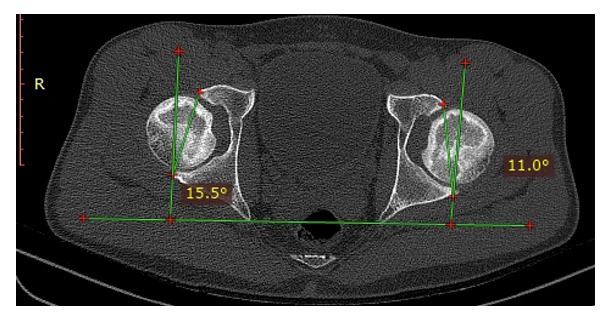

The acetabular anteversion angle was measured on the axial plane as the angle formed by the line connecting the anterior and posterior edges of the acetabulum with the line perpendicular to the line connecting the two ischial tuberosities (Image 3). The acetabular inclination angle was determined on the coronal plane as the angle formed by the line connecting the superior outer edge of the acetabulum and the “tear drop” with the horizontal line passing through the two ischial tuberosities (Image 4).